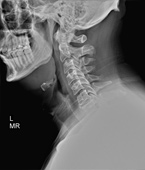

Before

After